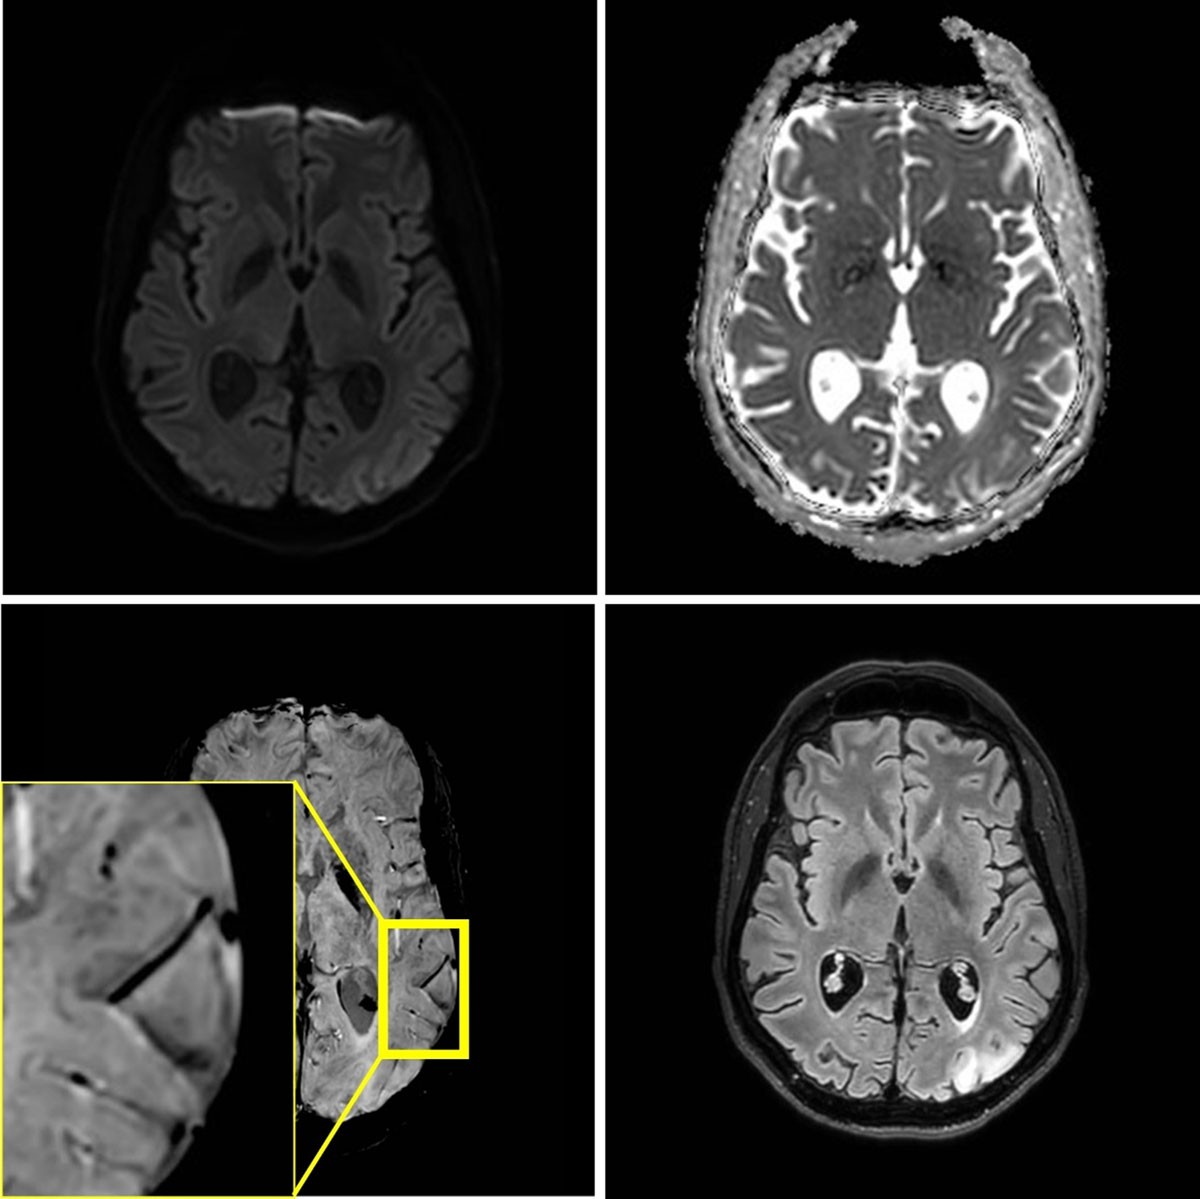

Figure 2

MRI at 3T performed three weeks later, because of a second stroke-like event. A similar lesion in the gyri of the left occipital lobe is present. Signal abnormalities in the previously affected area nearly normalized, but microhemorrhages persisted.

After three and seven weeks, two new stroke like-episodes occurred with similar imaging findings respectively in the left occipital region with right hemianopia, and in the left parietal region including the postcentral gyrus with right arm paresis and sensory deficits (Figures 2 and 3). Notably, at seven weeks, microhemorrhages were also present in the acute lesion. Signal abnormalities in previously affected areas nearly normalized, but microhemorrhages persisted.